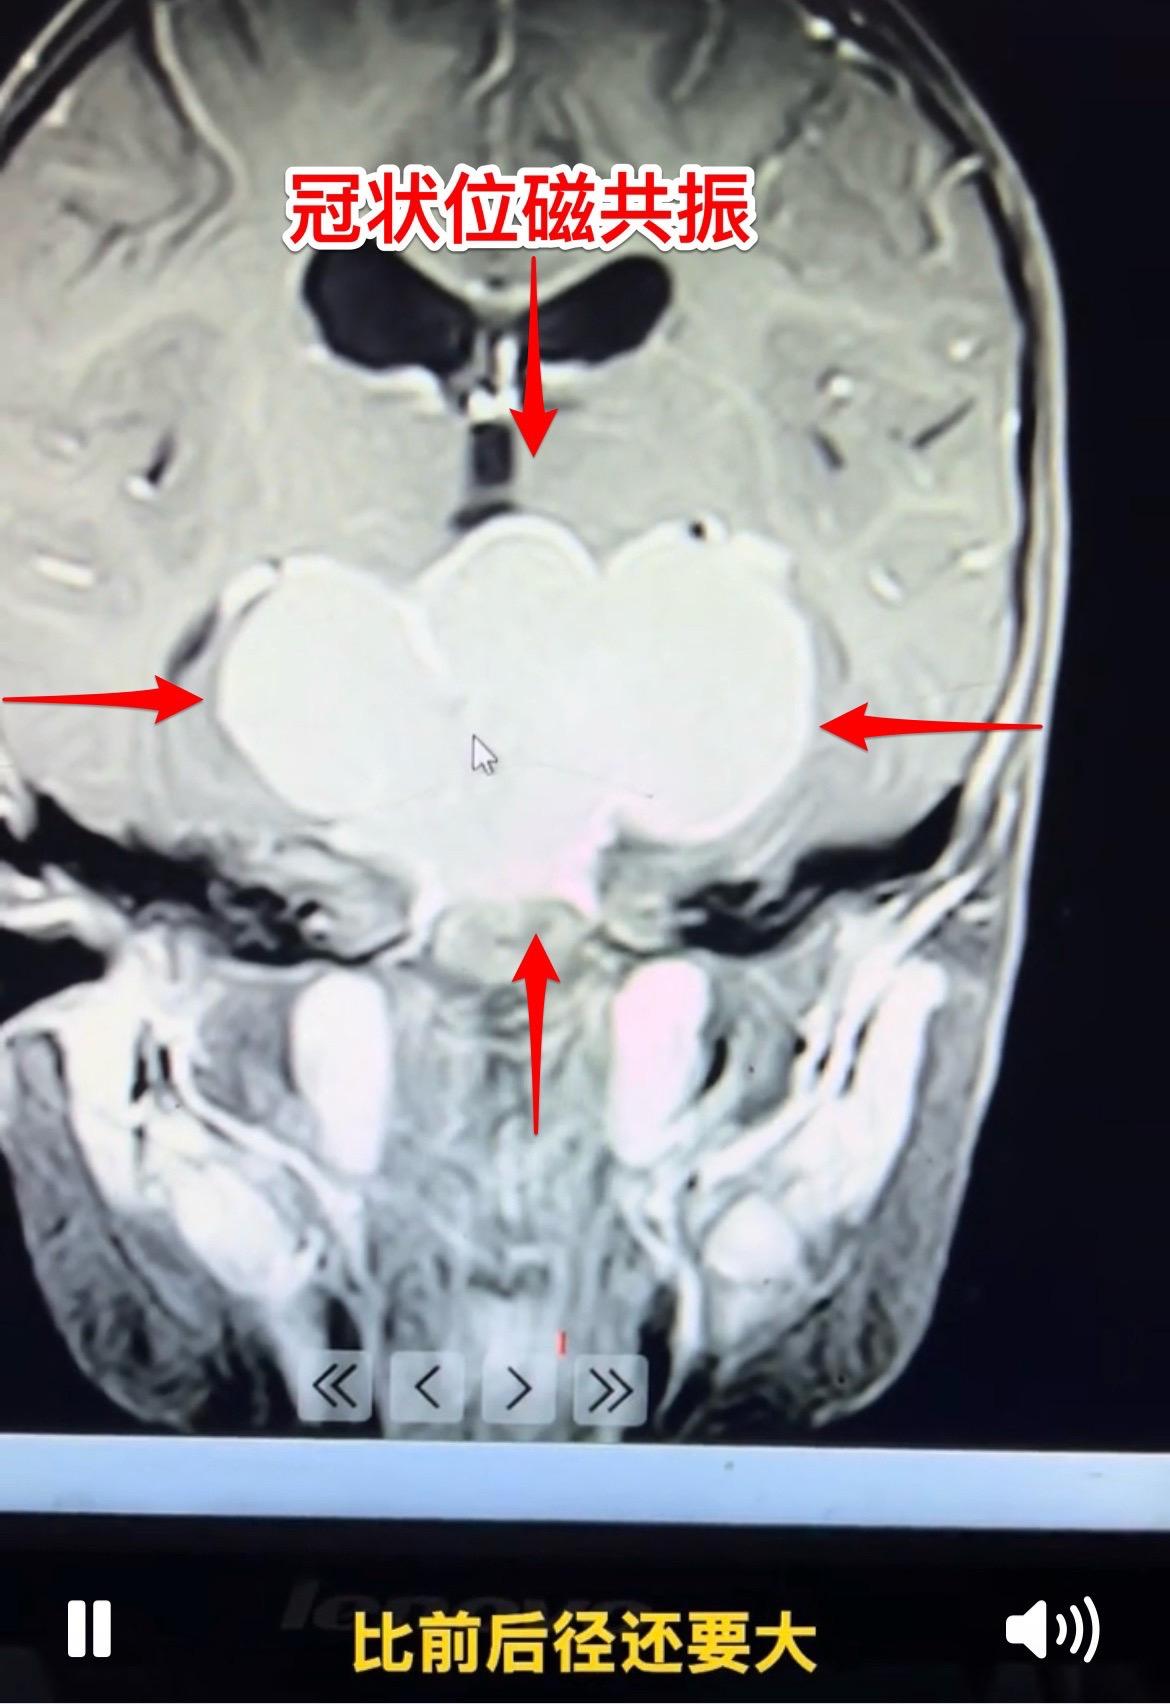

1岁10个月小孩子明天要作手术了。因为视力下降、眼睑下垂发现颅咽管瘤。 肿瘤的大小有多大?观众自己估量一下。 明天要给她作手术了,为她加油!预祝手术成功!